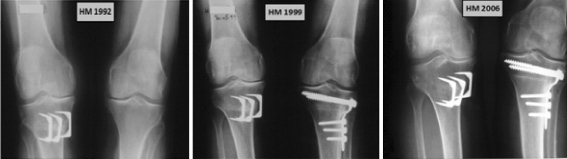

Moreover, Aglietti et al. [1] state that it is possible that the opening wedge technique creates less deformity than the closing with tibial metadiaphyseal mismatch that might interfere with a subsequent revision to TKR (Fig. 3).

Fig. 3.

A 63-year-old female patient (H.M.) who benefited from a right knee high tibial opening osteotomy in 1991 allowing the right medial compartment a quite good aspect for many years. In 1998, her left knee also deteriorated, which necessitated a closing procedure. The right medial joint space was looking quite nice in 1999, while a deformity of the closing osteotomy with tibial metadiaphyseal mismatch was visible on the left knee in 2002. At the last follow-up the knees were slight painful and the patient was walking with a cane